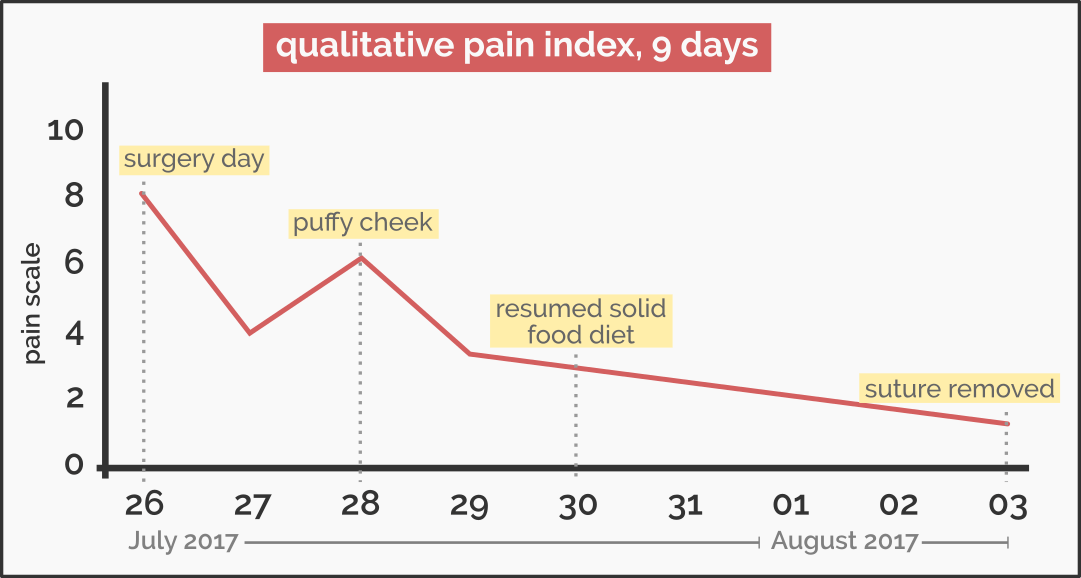

The following days starting from July 29 – Wednesday 5, I had to go to the Kuala Lumpur to complete my travel documentations at the U.S. Consulate and I needed to notify my sponsor (MARA) that I had graduated last May. Had I done this dental extraction a week earlier, I would’ve not attracted some attentions because my right cheek was so puffy and I kept on massaging my cheek like I just got punched with a chair in the face. Thankfully it was only one side. If both sides, I would have an appearance with the same quality of a pufferfish but with a lung and two pairs of limbs.

The swollen cheek took effect about two days post-surgery (on July 28). I woke up with a very weird feeling on my right jaw, and I thought I was still dreaming. I had this thought to punch my right jaw just to be sure but my subconscious self spared me pain from doing such a foolish act. The pain grew as the day passed to a point swallowing saliva felt like dragging my face on a hot tarmac. Yes I am exaggerating now so deal with it. But, it did not stop just there. In fact, the pain was coupled with canker sores. What a great time to have canker sores. If I counted correctly, I got three of them. What could be much worse than this, right?

On day 4, I started resuming solid food diet (rice, meat, noodles) after 3 days on soft food (yogurt, porridge, etc). I was careful enough not to overuse my right jaw. Brushing teeth required a little bit of attention to not aggravate the tooth socket. I noticed there was white precipitate like a puss. I was really curious to a point I touched it (don’t!) and tried to dislodge it with my tongue (a big, fat, obese, DON’T). It is called granulation tissue and it poses no threat. In fact, it is a sign of recovery and should not be touched with bare fingers.

The pain and swelling subsided on day 6 and eventually on day 9 (August 3), I had the suture removed. The removal of the suture was painless. On top of that, I had another minor treatment on that day to treat an infection for the tooth next to the extracted third molar. A dental filling was done with resin-based material and the whole thing took less than 15 minutes.